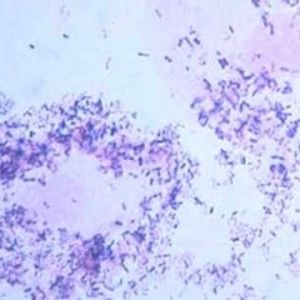

Традиционным и наиболее достоверным методом диагностирования уреаплазмоза является мазок из уретры. Берется при помощи специальной щеточки. Практически в каждом случае делается посев. Суть в следующем: материал пациента помещается в специальную питательную среду, после чего ведется наблюдение за развитием патогенных микроорганизмов.

Общий мазок не дает достоверности картины при выявлении уреаплазмоза, поскольку количество лейкоцитов при нем может быть либо незначительно повышено, либо соответствовать норме. Чтобы точно поставить диагноз необходимо использовать ПЦР и бактериальный посев. При ПЦР-анализе, подтверждающем наличие уреаплазмы, результатом станет показатель более 1,0*10^3 копий на 1 мл. При культуральном методе можно не только определить наличие уреаплазмы, но и провести анализ на чувствительность выделенного штамма к конкретным антибиотикам для более точного подбора лечения.